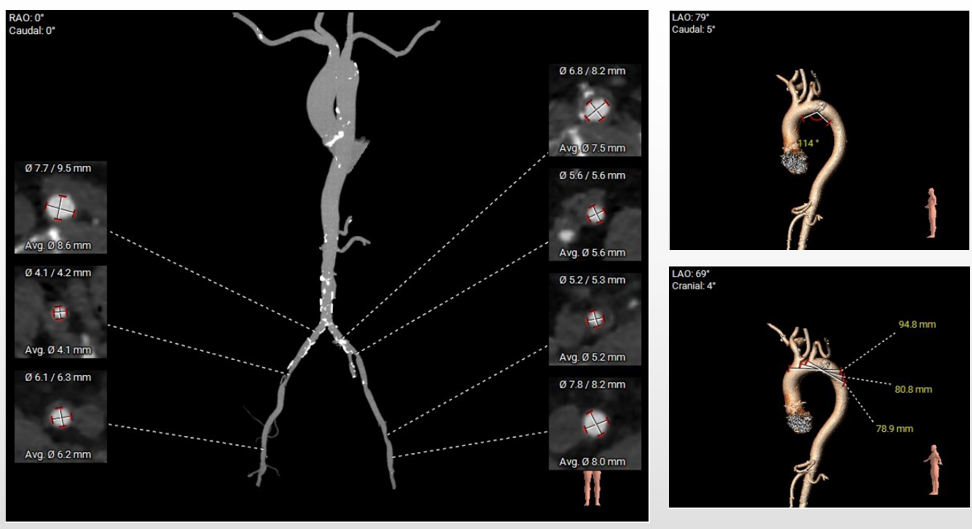

第二例术前评估

主动脉根部评估

三叶式主动脉瓣,瓣叶增厚,流出道呈直筒状,由于瓦氏窦、STJ内径小,左冠窦瓣叶长度>瓣叶附着缘到冠脉开口的距离,术中有冠脉阻挡风险。

瓣环上解剖结构评估

重度钙化,瓣上4-8mm限制最重,根据瓣环及瓣上情况,选20mm球囊预扩、AV23瓣膜。

外周血管及主动脉弓解剖

双侧髂总动脉轻度扭曲少量钙化,双侧髂外动脉内径细,左侧内径稍好,最细5.2mm,选择左侧为主入路,右侧为辅入路。